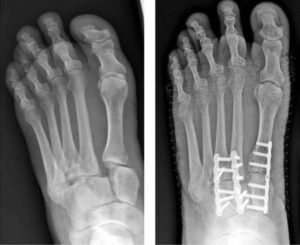

Various methods of internal fixation can be used to fix Lisfranc injuries depending on the injury pattern. (Left) Multiple screws can be used. (Center) A combination of plates and screws are sometimes required when fractures are present in addition to a torn ligament. (Right) Plates that span the joints are also an excellent method of fixation.

Radiographs showing a complete midfoot dislocation (left) before and (right) 2 years after fusion.